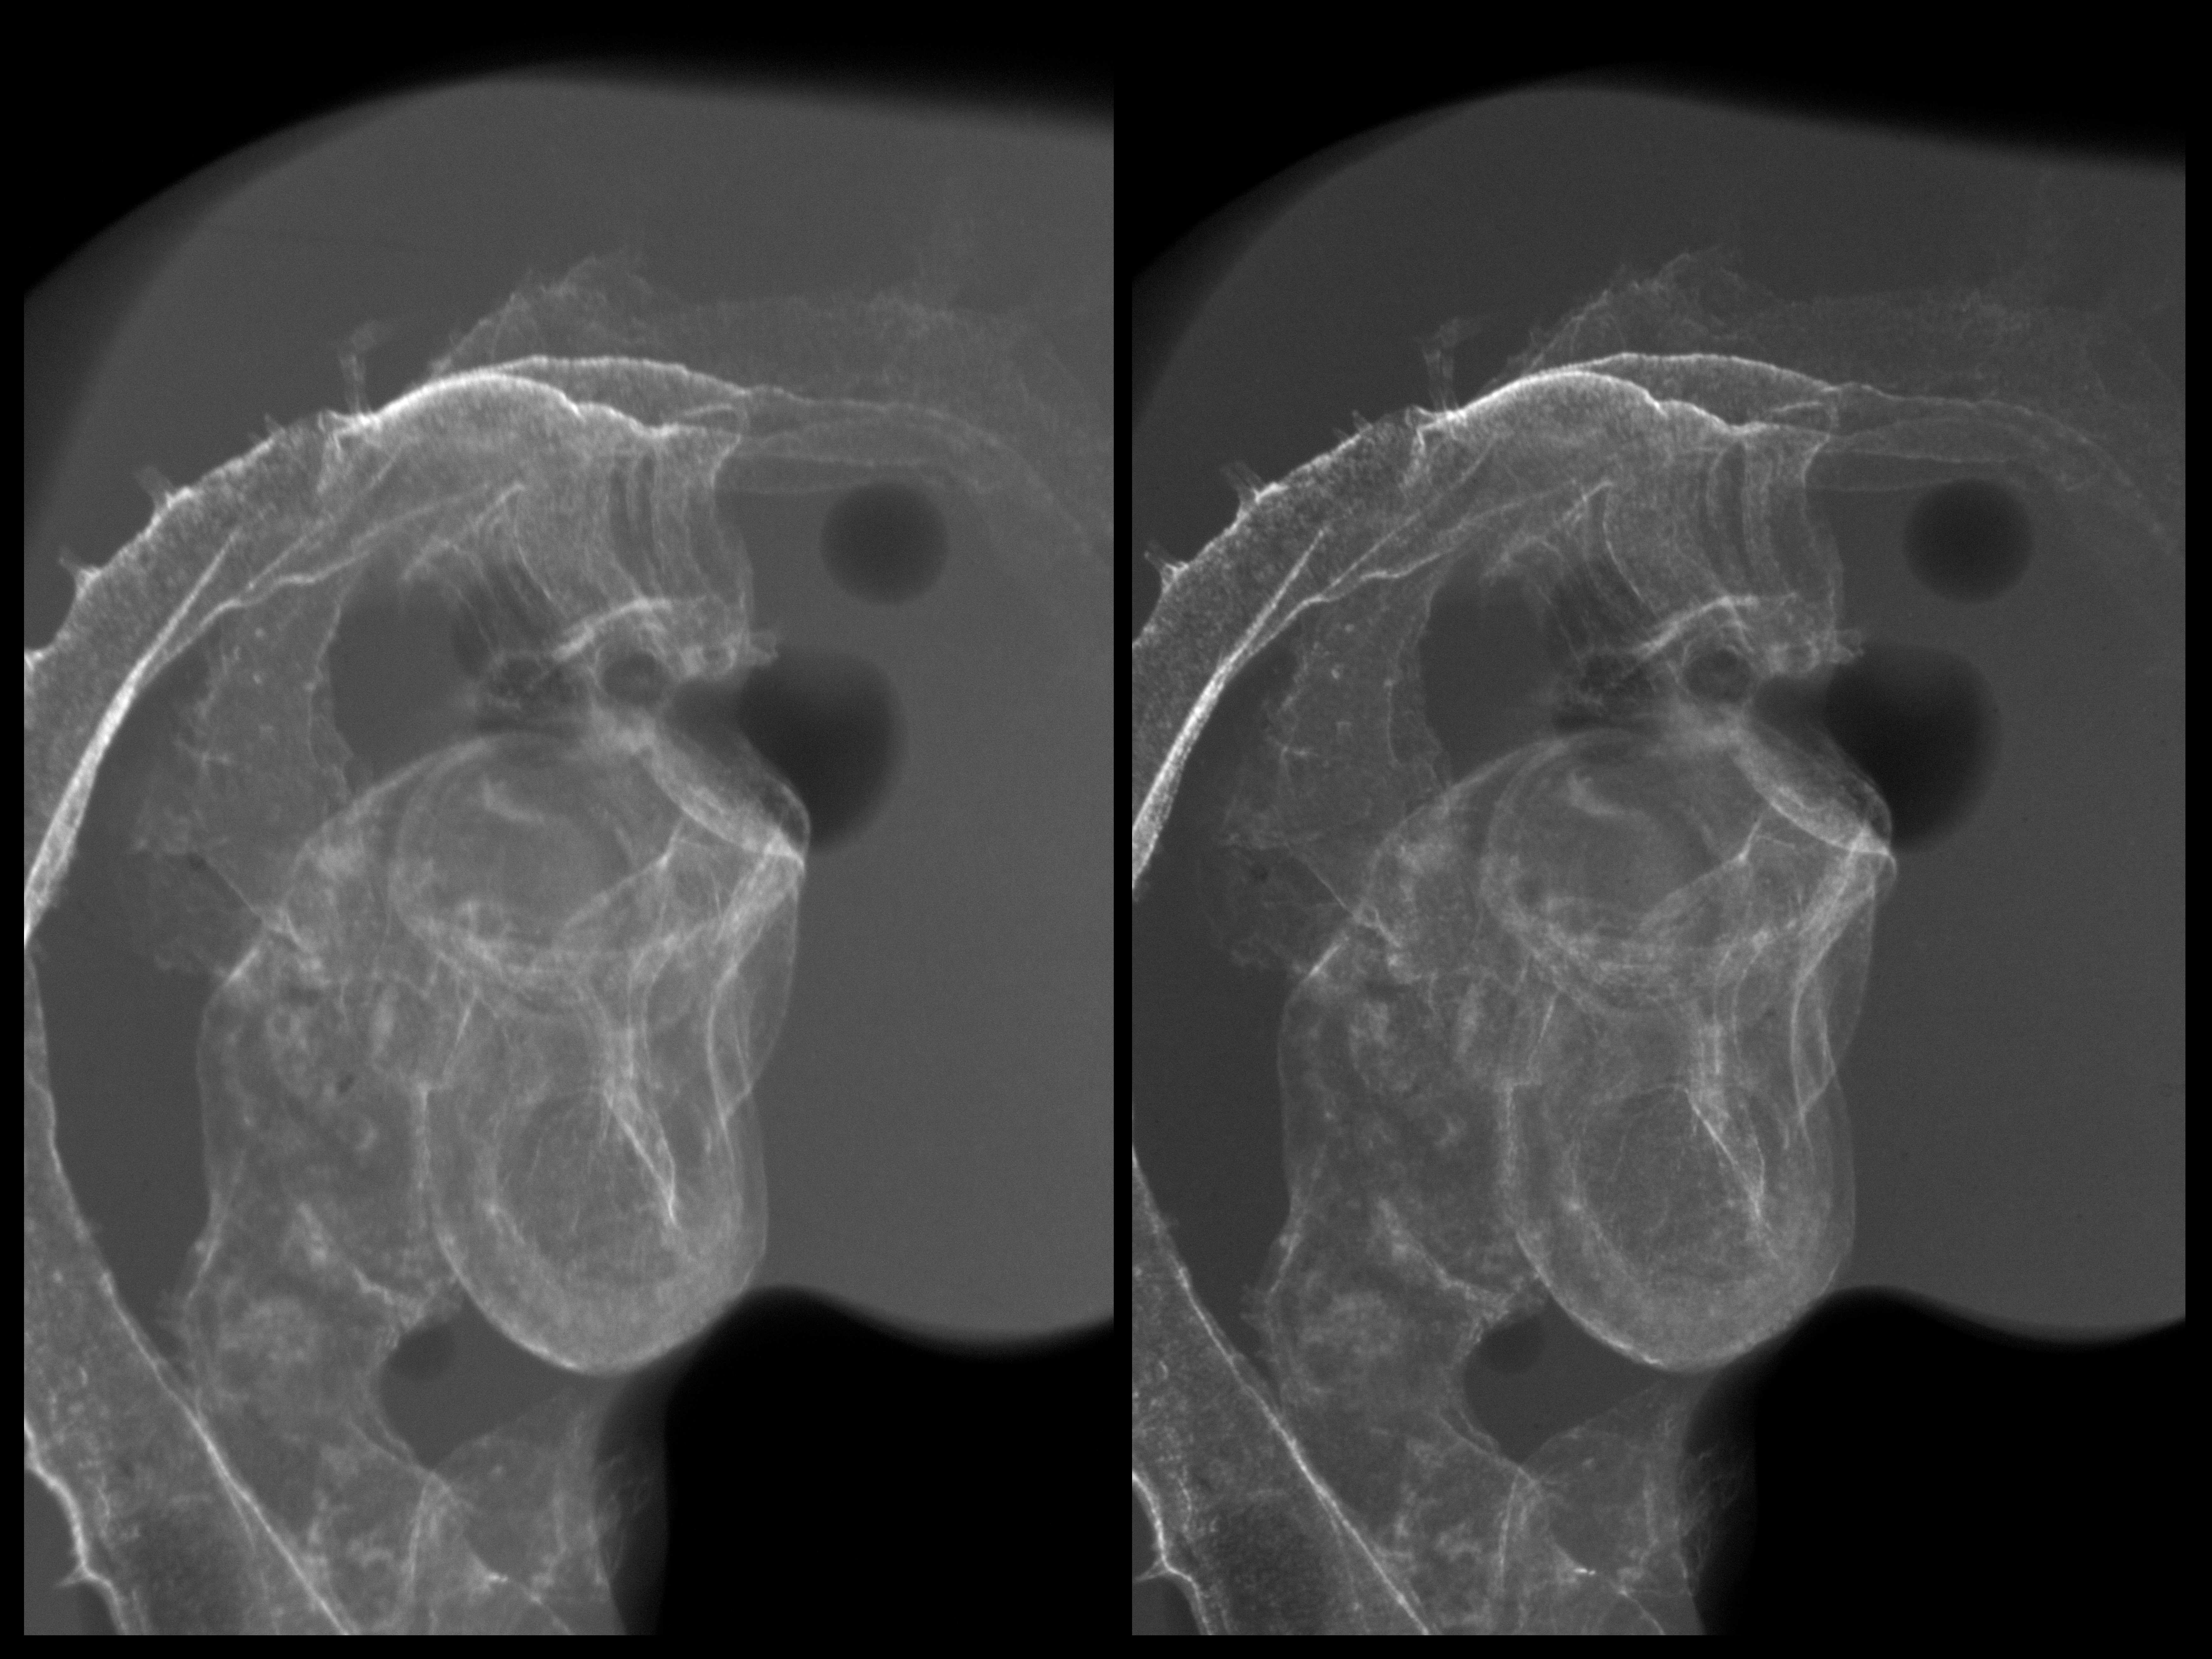

Stereo X-Ray Micrographs